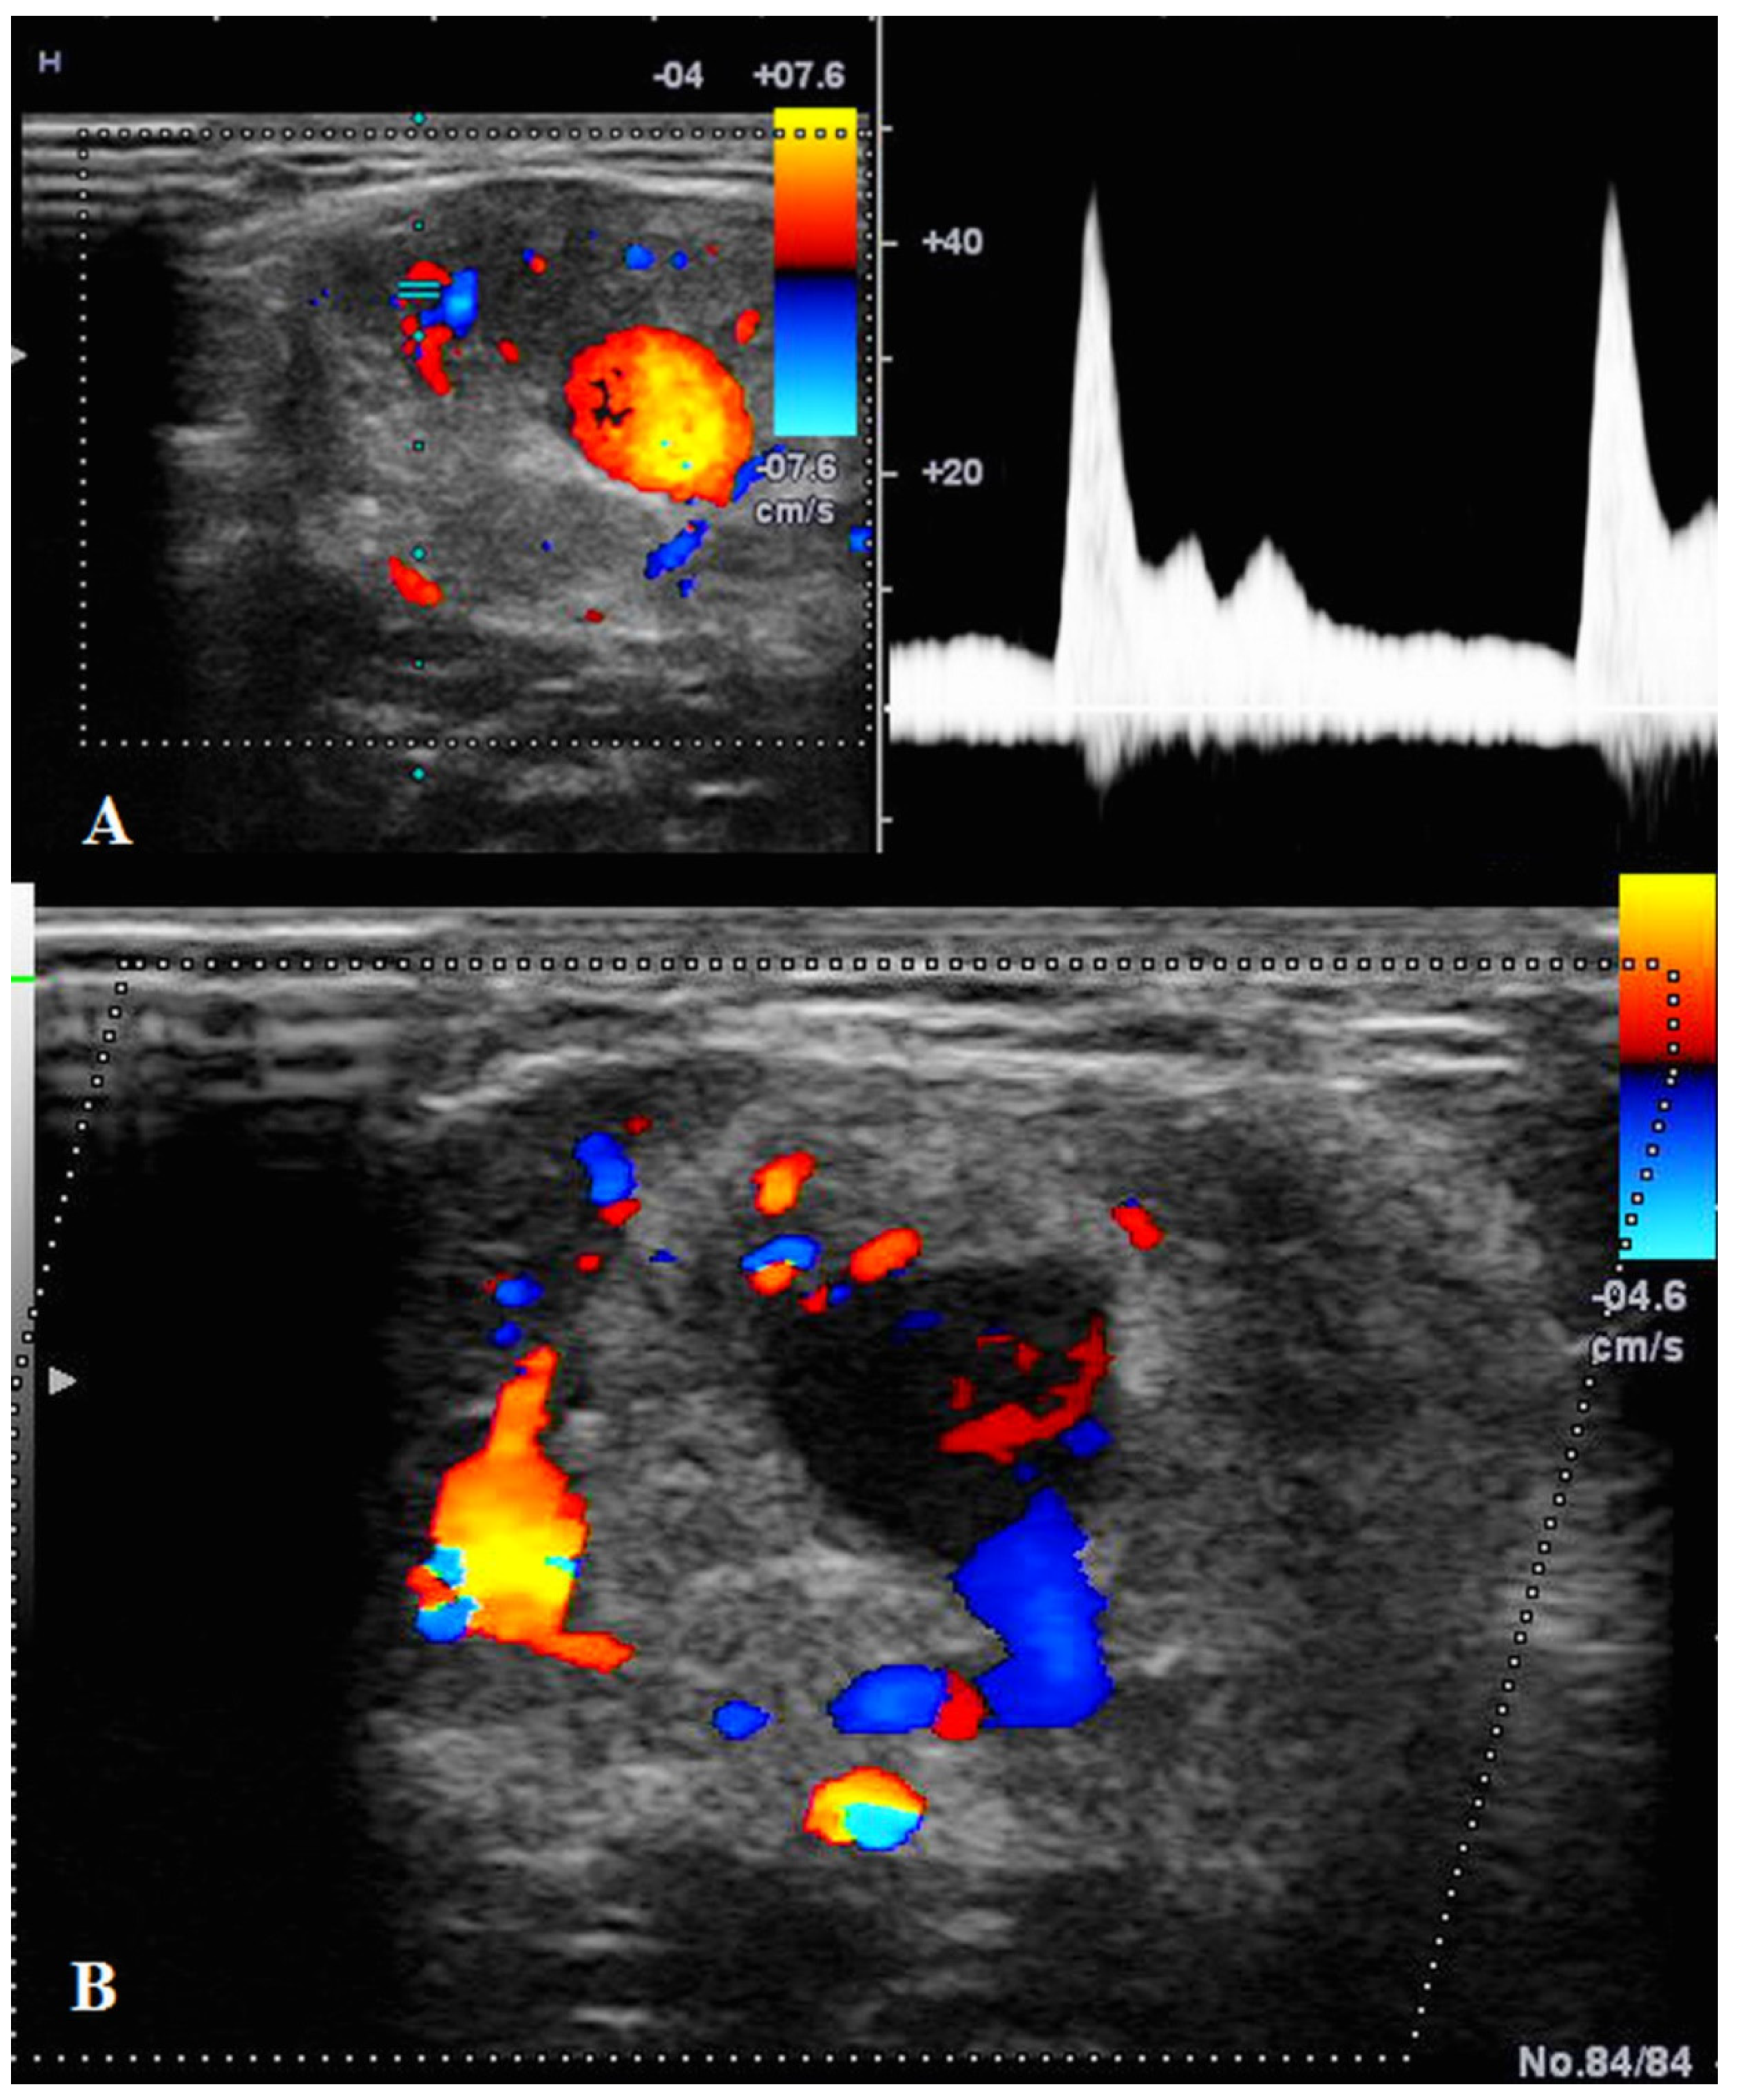

US showed a solid mass surrounding the brachial artery, located in the arterial wall, with a clear delimitation between the internal and external wall of the artery (Figure 2). The mass was encasing the artery’s lumen without stenosis at Doppler US (Figure 3A). The brachial vein and nerve were situated nearby without evident signs of tumor invasion nor growth around them. The solid mass had internal vascularity, with a small nutritive vessel originating from the brachial artery (Figure 3B).

Figure 3.

(A): Doppler US showed no stenosis of the brachial artery with good blood flow. (B): Doppler US showed the mass having a small nutritive artery originating in the brachial artery.

For our patient, US was the second-line imaging modality used to depict and characterize the mass. It helped not only to highlight the mass origin, but also to assess the vessel permeability. The nutritive arterial tumor vessel was well-depicted by the Doppler mode, which suggested an underling tumor process over an arteritis and had an important role in planning the surgery procedure.